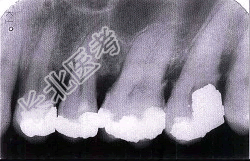

- 单项选择题牙槽骨水平型吸收的特点是( )

A、是最常见的吸收方式

B、牙槽间隔、唇颊侧或舌侧的嵴顶边缘呈水平吸收

C、牙槽嵴高度有明显降低

D、常形成骨上袋

E、以上均是